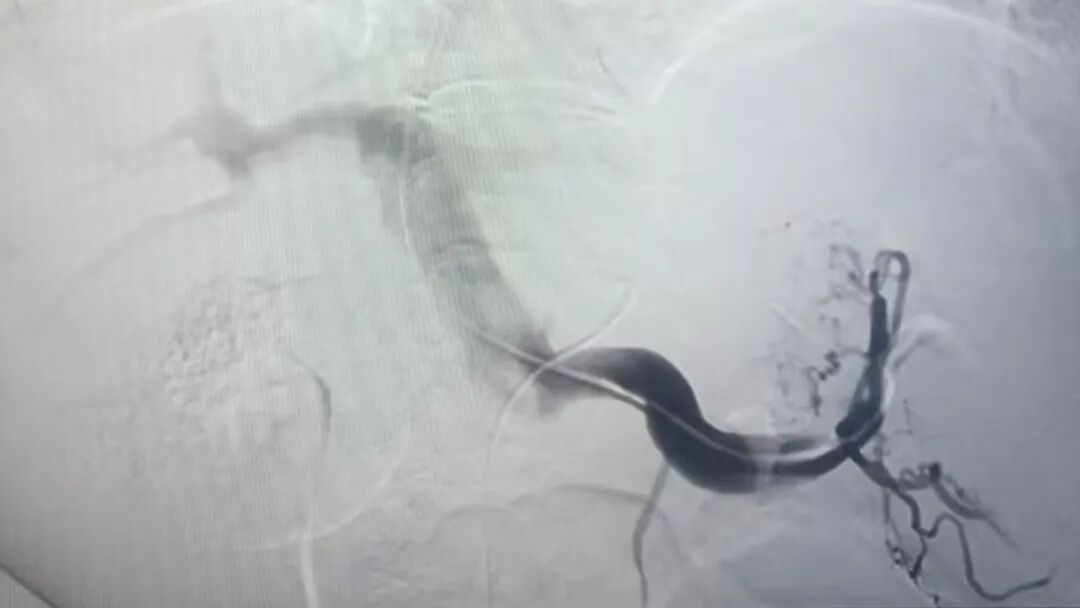

手术当晚,挑战超乎想象。术中,李家平教授发现赵先生的肝脏严重萎缩,血管扭曲变形,门静脉右支被血栓堵了90%,操作空间极为狭小。李家平教授当机立断,决定从左支突破,但左支的血管又细又与门静脉紧密相邻,稍微扎偏一点就可能导致严重出血。关键时刻,李家平教授凭借精湛的技术和丰富的经验,像穿针引线一样,精确地从肝右静脉精准“穿针”到门静脉左支矢状部,每一个动作都精准无误,成功架起支架。